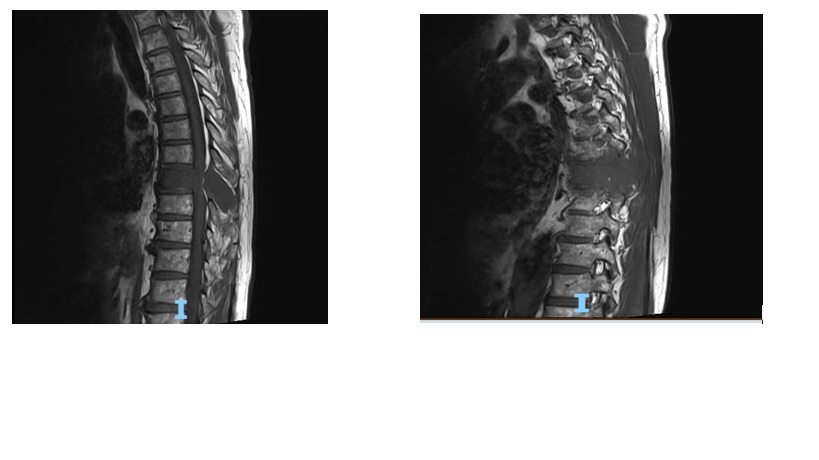

MRI cột sống ngực

Hình 3

Kết quả MRI cột sống ngực có gadolium:

Thâm nhiễm tủy xương đốt sống ngực T8 lan ra mô mềm xung quanh và vào ống sống chèn ép tủy

Chẩn đoán xác định: chèn ép tủy sống ngực T8